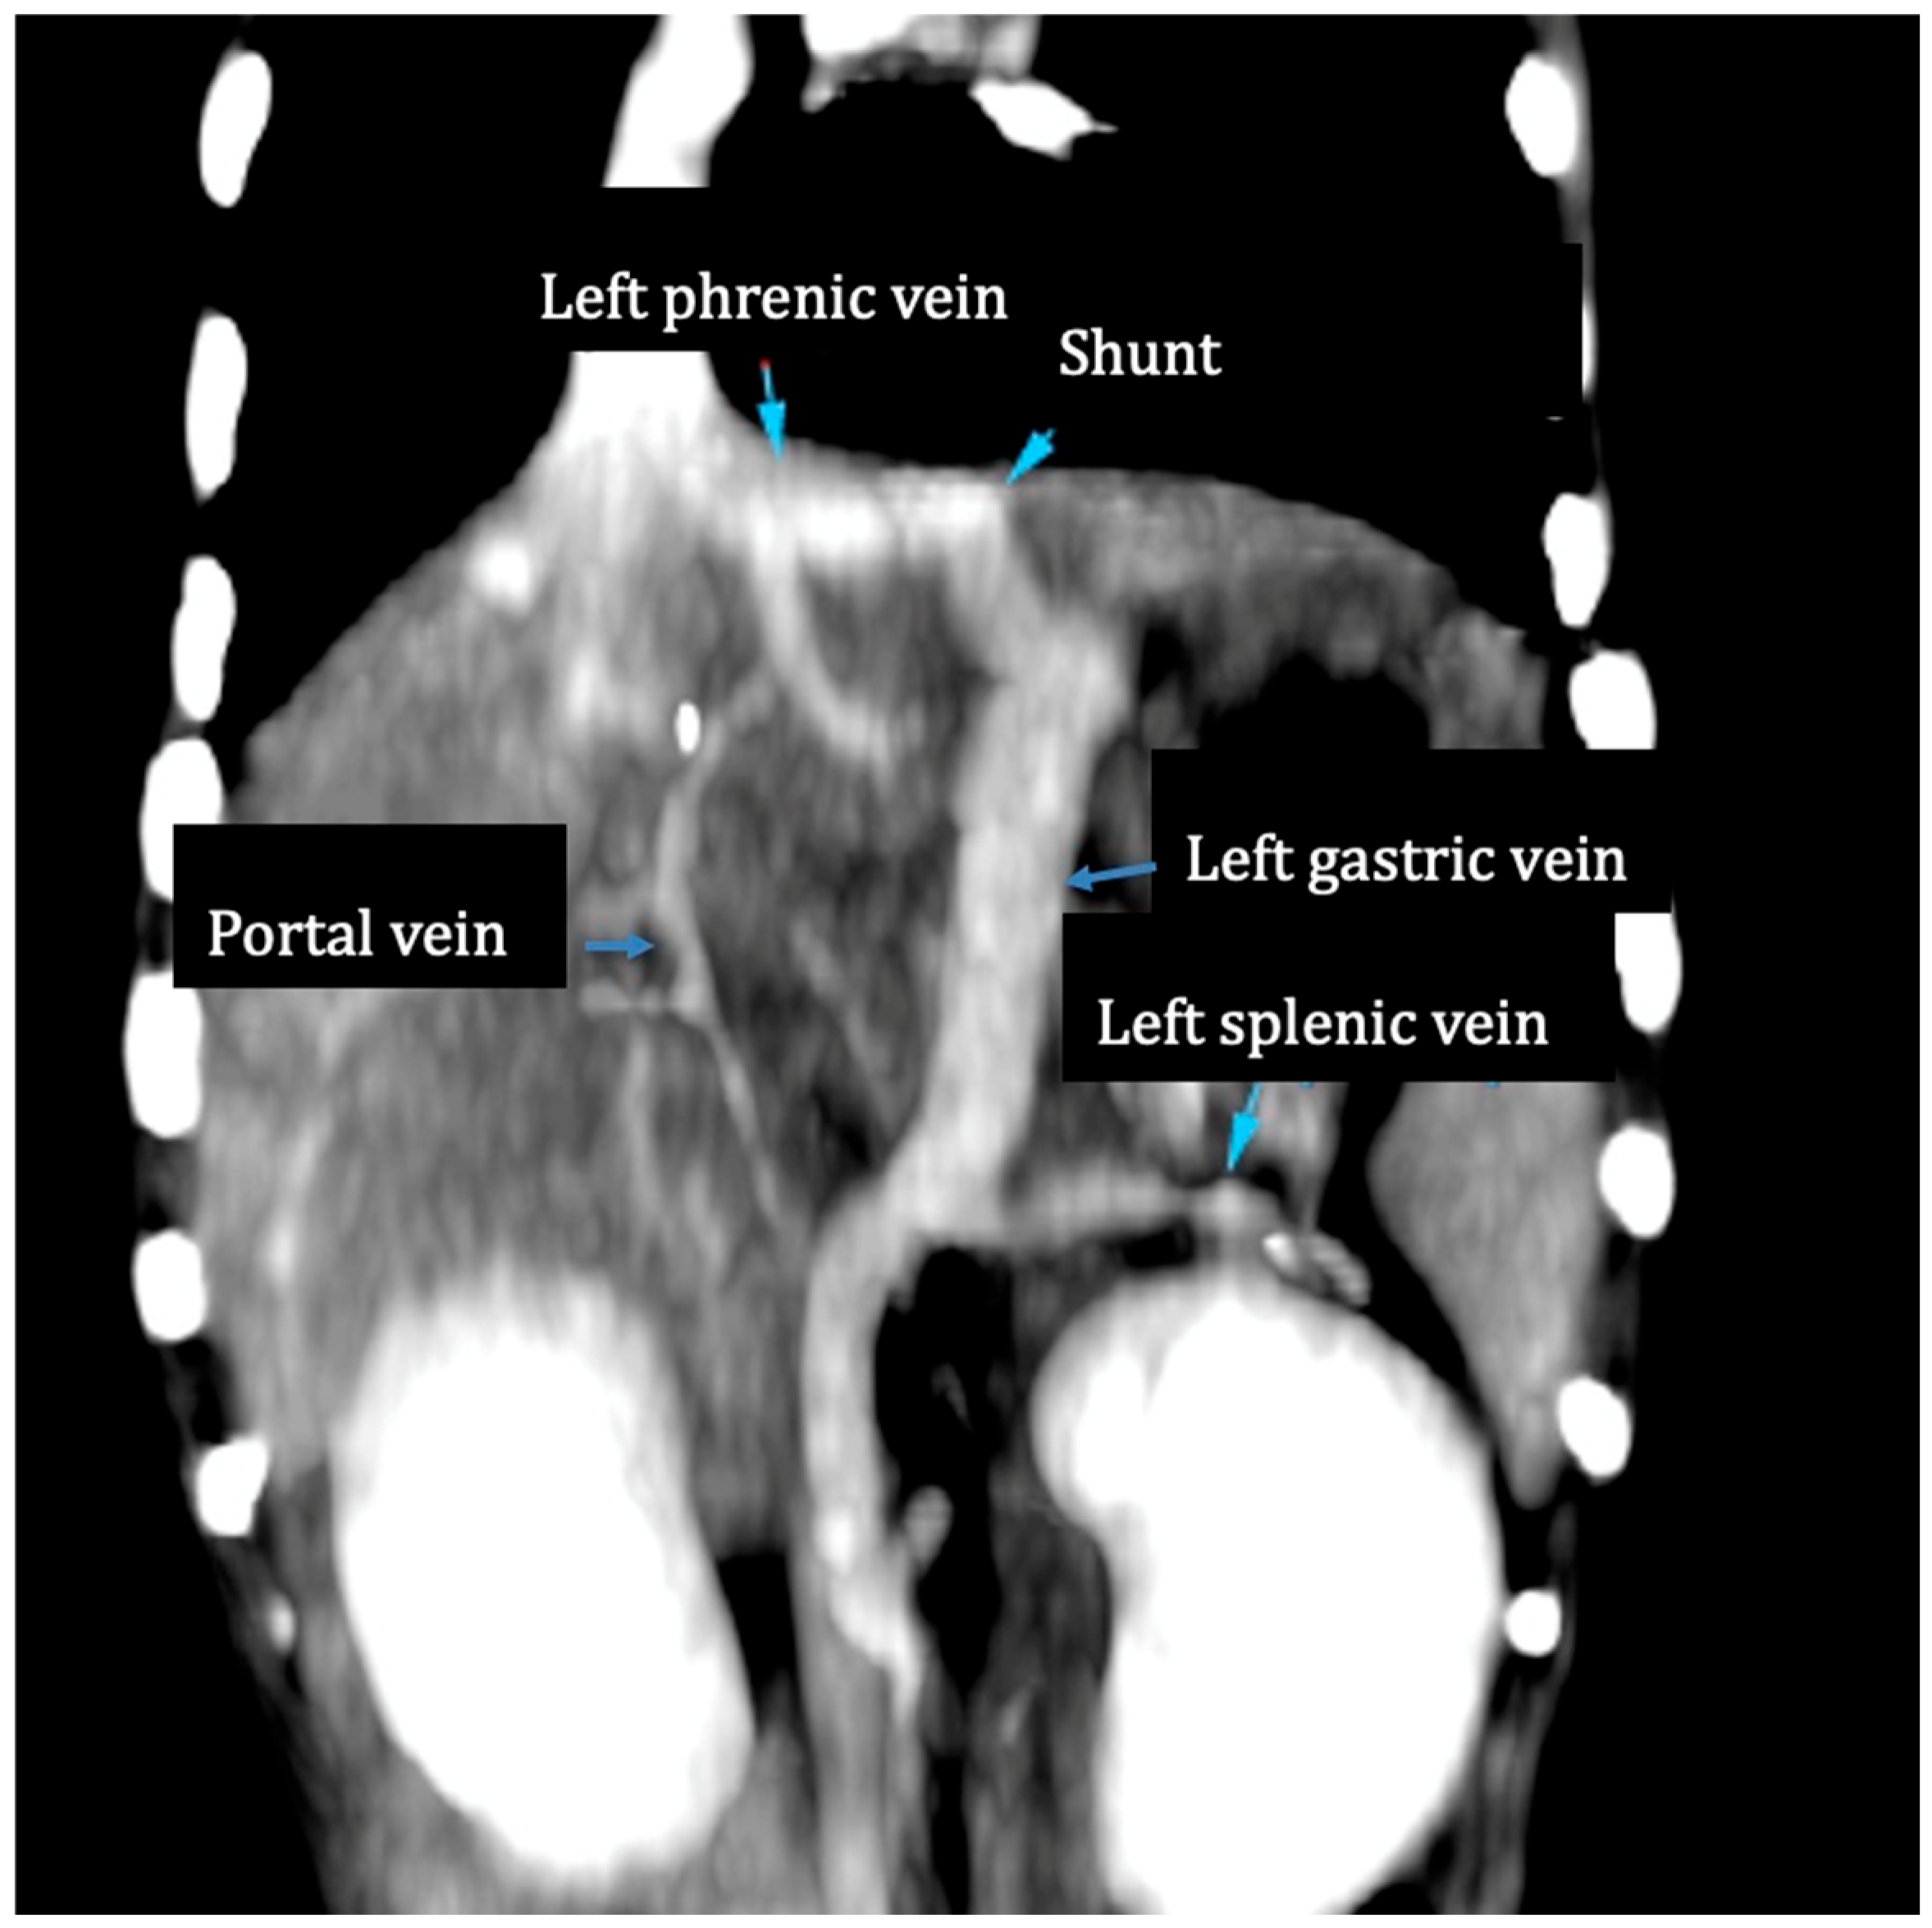

A preoperative CT angiography was performed in 11 patients (Figure 2). Abdominal ultrasonography was the only diagnostic exam available for one dog. The mean diameter of the shunts was 6.1 mm (range: 4.2–8).

Figure 2. Post-contrast CT angiography. An enlarged left gastric vein joins the left phrenic vein at the level of the esophageal hiatus.